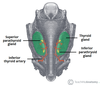

What is this muscle?

What is this muscle?